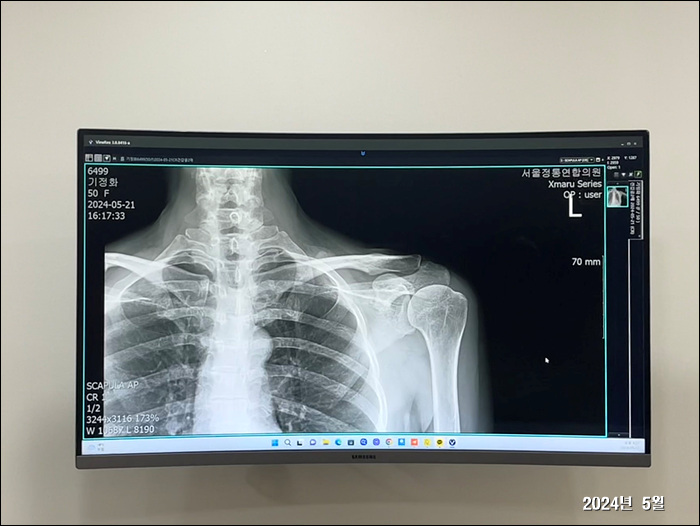

2024. 5. 21.

정화 오십견 진단

의정부에 일하러 갔다가... 병원가서 오십견 진단 받고옴.

팔이 갈수록 아파서 위로는 잠도 못자고... 힘든 하루 하루를 보내고 있음